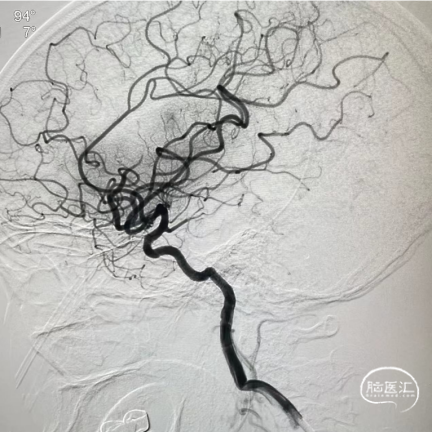

术前造影

术后造影